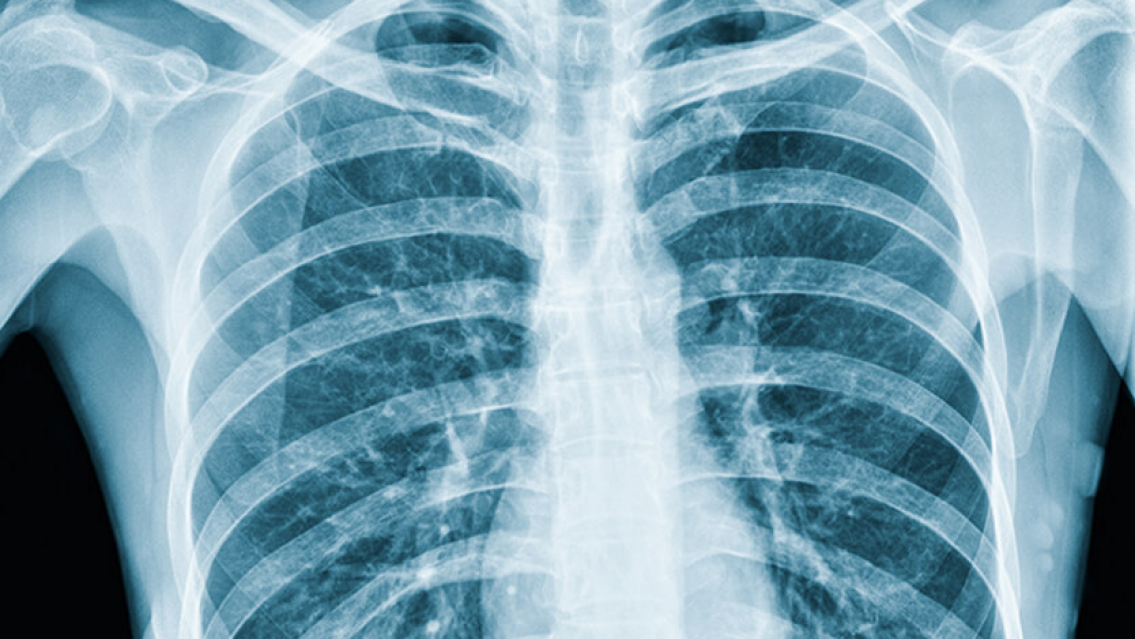

El interno fue revisado por el médico de turno en la cárcel, quien ordenó su traslado al Hospital Carlos Snopek para realizar radiografías y confirmar la presencia de cuerpos extraños en su abdomen. Las placas revelaron varios objetos extraños, por lo que se informó al auditor del establecimiento penitenciario y se contactó al fiscal, quien dispuso que el interno permaneciera en el área judicial hasta evacuar los elementos ingeridos mediante la administración de laxantes.